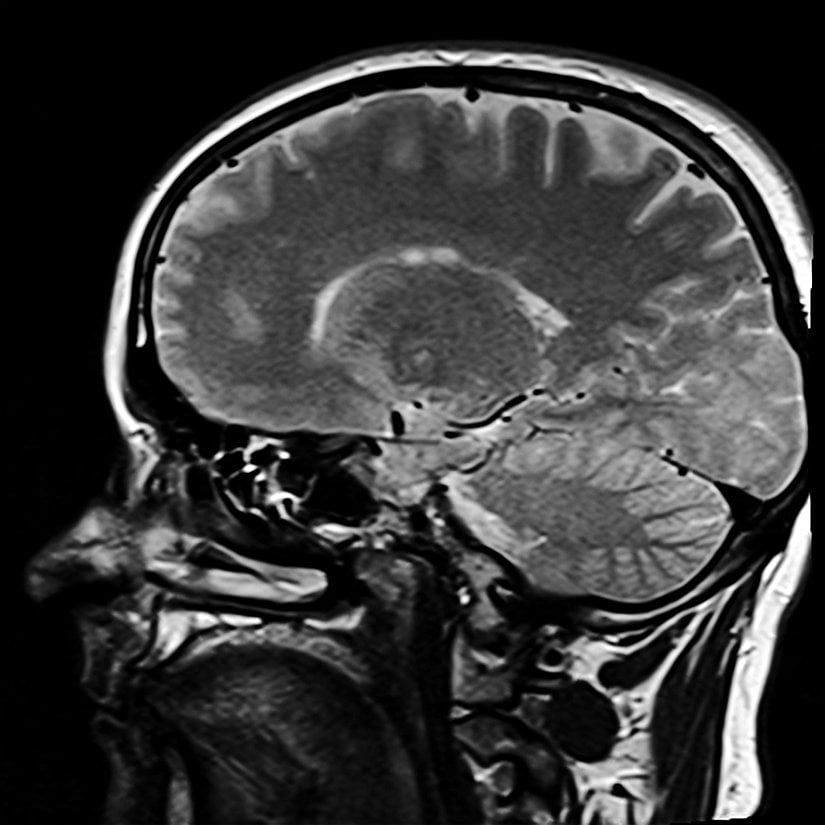

Ceza hukuku kapsamında, işlenen suçun tekrarlanma ihtimali yargı uzmanlarınca endişe edilen konulardan biridir. Bu hususta, suç içerikli davranışları, beyinde uyardıkları bölgeler ve harekete geçirdikleri nöronları izleyerek analiz eden görüntüleme cihazlarına başvurulmuştur. Nitekim, beyin görüntüleme cihazları aracılığıyla elde edilen bu görüntülerin kontrolsüz dağıtımı yahut karşı tarafa sızdırılması durumlarında, mahkemelerin haksız hükümler verebileceği göz önünde bulundurulmalıdır. Görüntülerin işin ehli nörobilimcilerden bağımsız, yargıçların hipotezlerinden yola çıkarak değerlendirilmesi sonucunda kamu güvenliği büyük ölçüde sarsılacaktır.